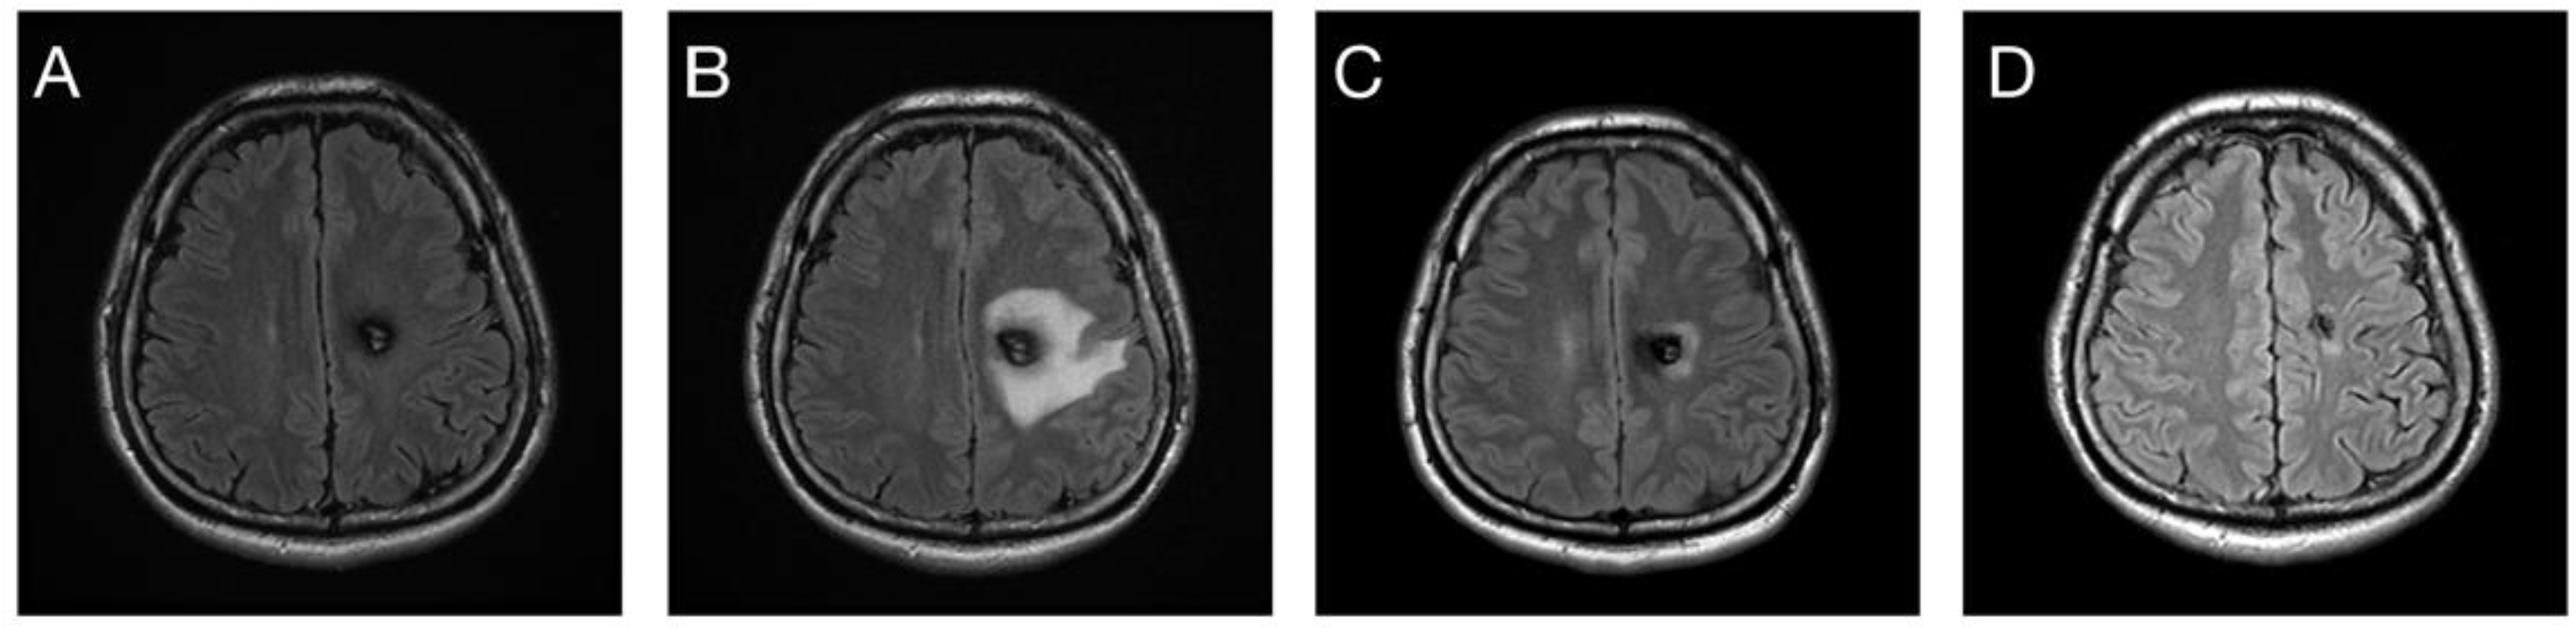

3.4. Post-Radiosurgical Perifocal Brain Edema

4.3. Post-Radiosurgical Adverse Radiation Effects